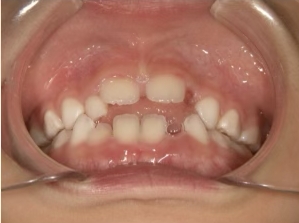

治療中➁ 小3:9y1m

前歯をブラケットで並べる